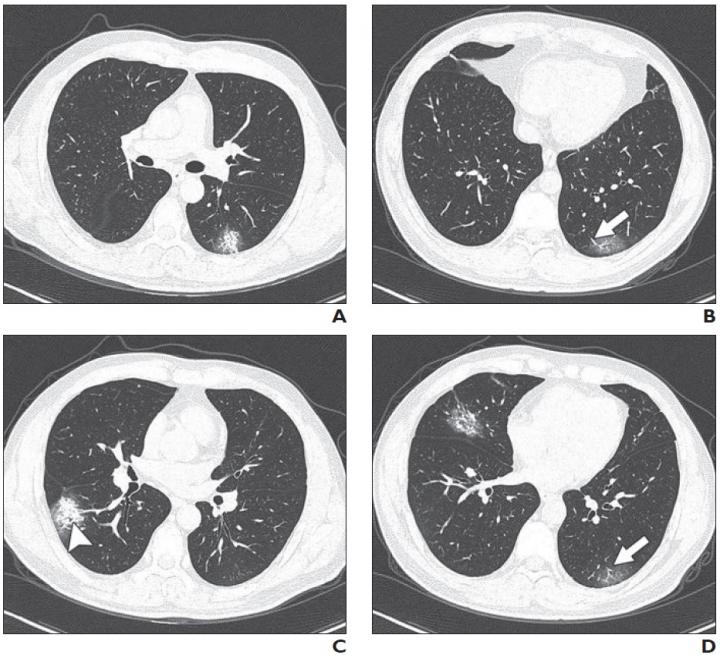

image: Patient had short-term exposure history to Wuhan and onset symptoms of fever (38°C) and cough. CT was performed on day of admission. A-D, CT images show bilateral multifocal ground-glass opacities (GGO) and mixed GGO and consolidation lesions. Traction bronchiectasis (arrowhead, C) and vascular enlargement (arrow, B and D) are also present. CT involvement score is 5.

Leesburg, VA, March 3, 2020--A multi-center study (n=101) of the relationship between chest CT findings and the clinical conditions of coronavirus disease (COVID-19) pneumonia--published ahead-of-print and open-access in the American Journal of Roentgenology (AJR)--determined that most patients with COVID-19 pneumonia have ground-glass opacities (GGO) (86.1%) or mixed GGO and consolidation (64.4%) and vascular enlargement in the lesion (71.3%).

In addition, lead authors Wei Zhao, Zheng Zhong, and colleagues revealed that lesions present on CT images were more likely to have peripheral distribution (87.1%) and bilateral involvement (82.2%) and be lower lung predominant (54.5%) and multifocal (54.5%).

As Zhao and Zhong explained further: "Architectural distortion, traction bronchiectasis, and pleural effusions, which may reflect the viral load and virulence of COVID-19, were statistically different between the two groups and may help us to identify the emergency type disease."

The authors of this AJR article also noted that CT involvement score can help evaluate the severity and extent of COVID-19 pneumonia.